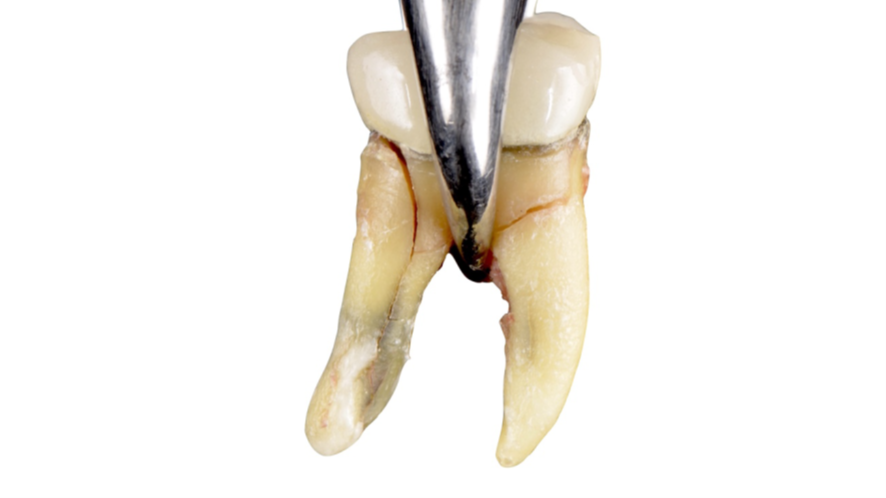

Mulher de 48 anos, sem antecedentes médicos relevantes, procurou atendimento odontológico com queixa principal de dor contínua em região do primeiro molar inferior direito. Na avaliação clínica foi observado uma fístula na vestibular do dente 46 (Figura 1) e a tomografia revelou uma fratura longitudinal, comprometendo a manutenção deste dente (Figura 2). Confirmada a necessidade de exodontia, foi planejada a instalação de um implante imediato e a confecção de um cicatrizador personalizado diretamente na plataforma do implante com um pilar provisório de titânio. Foi realizada uma extração dentária minimamente traumática visando preservar a integridade dos tecidos moles e duros circundantes (Figuras 3 e 4).